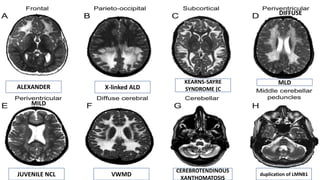

ALEXANDER X-linked ALD

KEARNS-SAYRE

SYNDROME (C

MLD

JUVENILE NCL VWMD

CEREBROTENDINOUS

XANTHOMATOSIS

duplication of LMNB1

DIFFUSE

MILD

ALEXANDER X-linked ALD KEARNS-SAYRE SYNDROME(C MLD JUVENILE NCL VWMD CEREBROTENDINOUS XANTHOMATOSIS duplication of LMNB1 DIFFUSE MILD